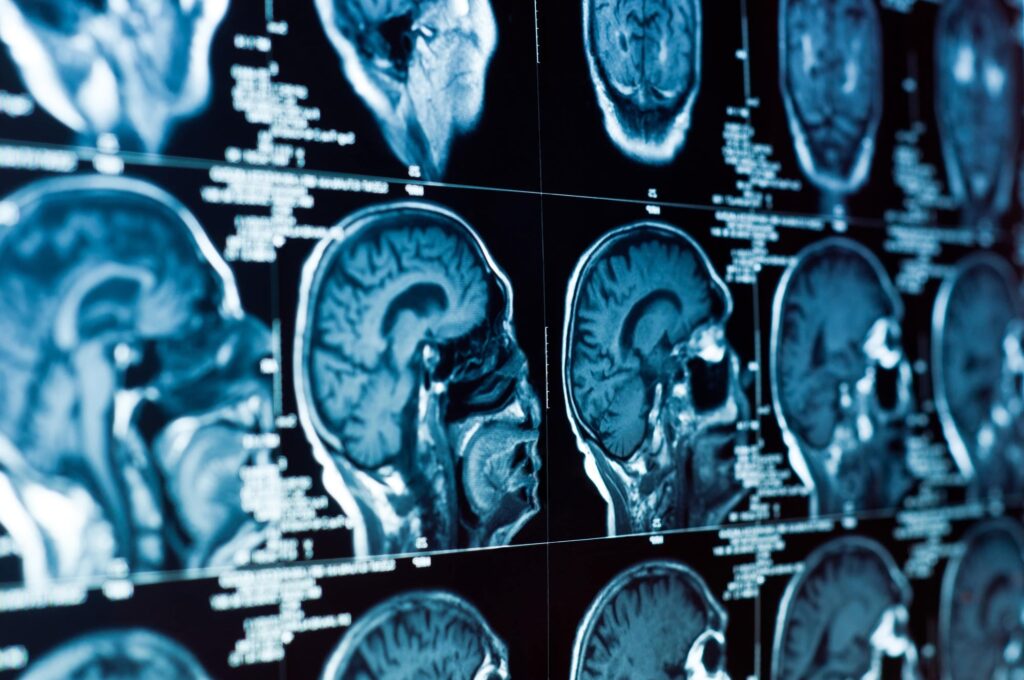

Even low-speed impacts can generate enough force to jostle the brain. Sudden stops, seatbelt tension, or unexpected rotation of the head can cause brain movement inside the skull. That motion is enough to create microscopic injuries that don’t show up on scans but still affect function.

These are often diagnosed later as mild traumatic brain injuries (mTBIs), but the symptoms can be far from mild. They tend to not show up immediately after an accident, but they develop over time.